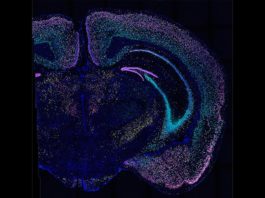

Reparan un defecto de reciclaje mitocondrial relacionado con la enfermedad de...

El tratamiento de ratones que tienen una mutación que causa la enfermedad de Parkinson con un compuesto de molécula pequeña restaura la eliminación de...